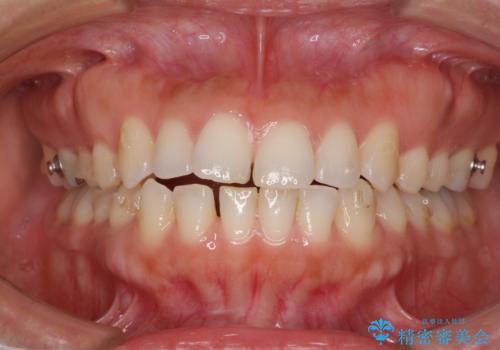

受け口傾向の前歯 すきっ歯の改善

- 前歯の隙間と口元の突出感を気にして来院された患者様です。

嚥下時に舌を突出させる癖があり、成長期に下顎が有意に成長し、歯と歯の間に隙間ができてしまいました。

舌の癖を改善し、インビザラインにて治療を行うこととしました。

舌癖を改善したことで、隙間や突出感を改善することができました。

隙間は後戻りしやすいため、舌側を細いワイヤーで固定することとしました。